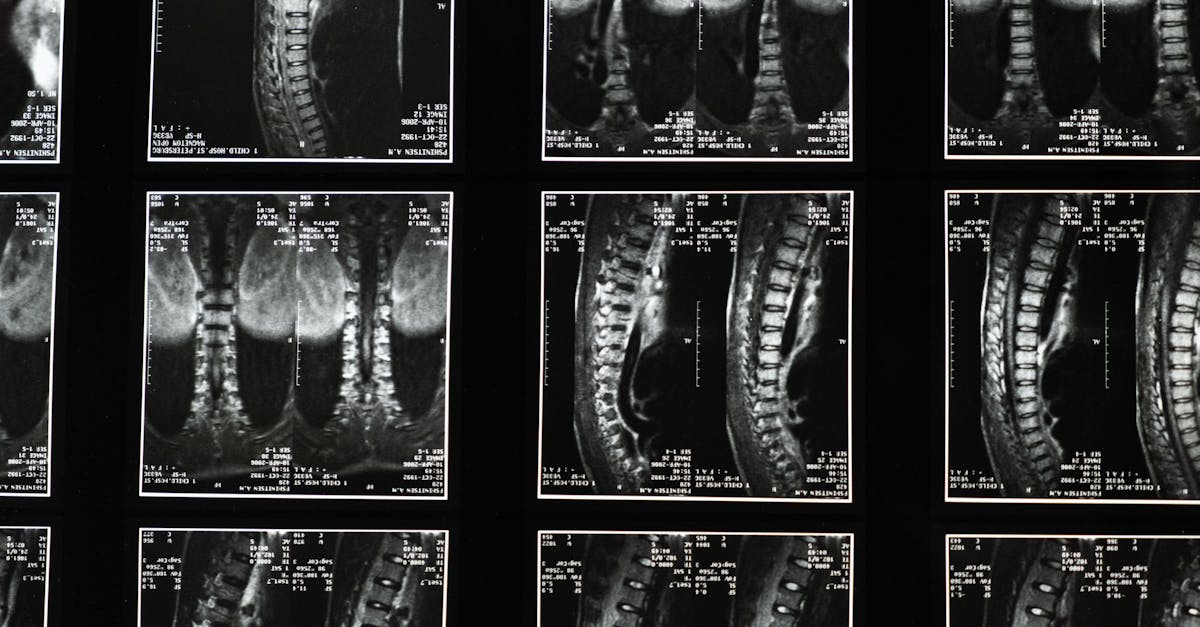

Sciatica, often characterized by lower back pain and discomfort radiating through the leg, affects millions of individuals, disrupting daily activities and degrading overall quality of life. At Pulse Align, our innovative approach centers around neuromuscular health and posture improvement through holistic recalibration. This article delves into how these subtle realignment techniques not only alleviate sciatica pain relief but also empower individuals to embrace a life free from the physical constraints of persistent discomfort.

Pulse Align employs gentle techniques designed for core strengthening and posture correction. This approach places emphasis on addressing the underlying causes of lower back pain, like herniated discs and spinal stenosis. Utilizing lower back pain exercises such as pelvic tilts, our method encourages natural balance and stability in the spine, ultimately resulting in significant pain reduction.

Are you struggling with chronic back pain or symptoms associated with a herniated disc or a bulging disc? TAGMED’s advanced Spinal Decompression Therapy offers a non-surgical solution designed specifically to address moderate-to-severe disc issues. By gently reducing pressure on the affected discs and nerves, this specialized technique helps enhance mobility, alleviate pain, and support your body’s natural healing process. If you’ve reached a plateau with other therapies, discover how TAGMED’s evidence-based decompression approach can help you resume an active, comfortable life.

The mechanism of action behind TAGMED’s neurovertebral decompression involves applying a controlled, progressive traction force to the spine. This innovative approach increases the space between vertebrae, effectively reducing pressure on intervertebral discs and nerve roots. By promoting better fluid circulation in the targeted area, the therapy helps to lower inflammation and relieve pain. This method provides a reliable, non-invasive solution for individuals suffering from chronic back issues, including sciatica and spinal stenosis.